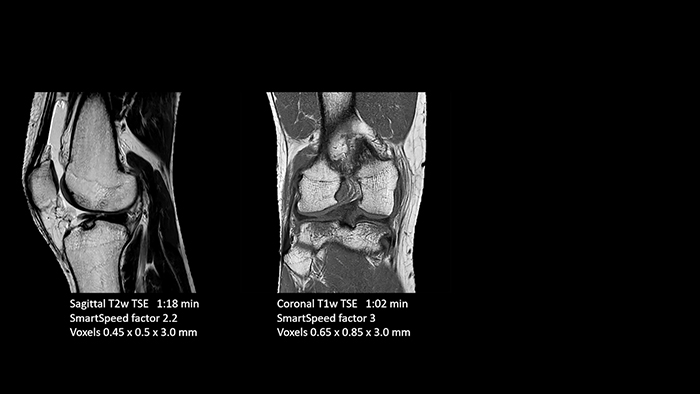

A leap in MSK imaging thanks to SmartSpeed

Previously, the practice wasn’t able to use 3D imaging on all joints, because the time required was too long, and on some joints it was simply not possible to achieve a good quality image, Dr. Schröter says. “Now, with SmartSpeed we consistently use 3D imaging for all joints and can thus discover the smallest changes, for example in the cartilage. And that, of course, helps us in making a detailed diagnosis.”

Dr. Schröter says their MSK images show high contrast and extremely high quality. He mentions the menisci as an example. “We use a 3D proton density weighted fatsat sequence, thickness is 0.3 mm and scan time 3 minutes. The MPRs show an unbelievable resolution. Very small tears and even fraying of the tip of the meniscus become visible, which is normally only possible in arthroscopic surgery.

With these 3D scans we can create freely selectable MPRs that are pin-sharp, allowing us to easily see pathological changes.”

Dr. Tobias Schröter